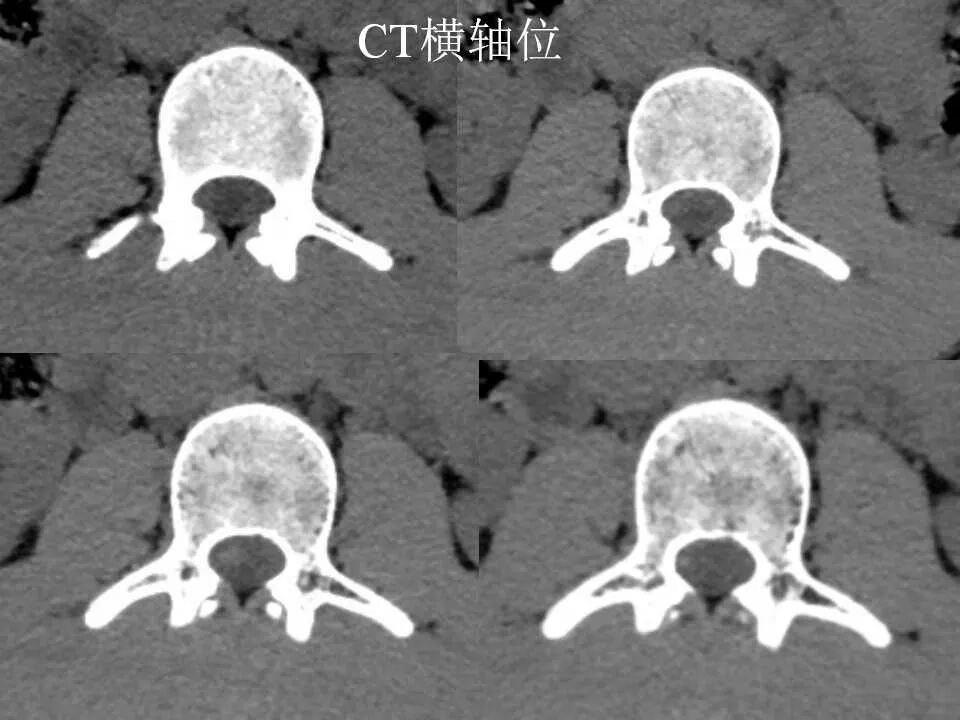

北方影像联盟 一周病例精选之“椎管占位”